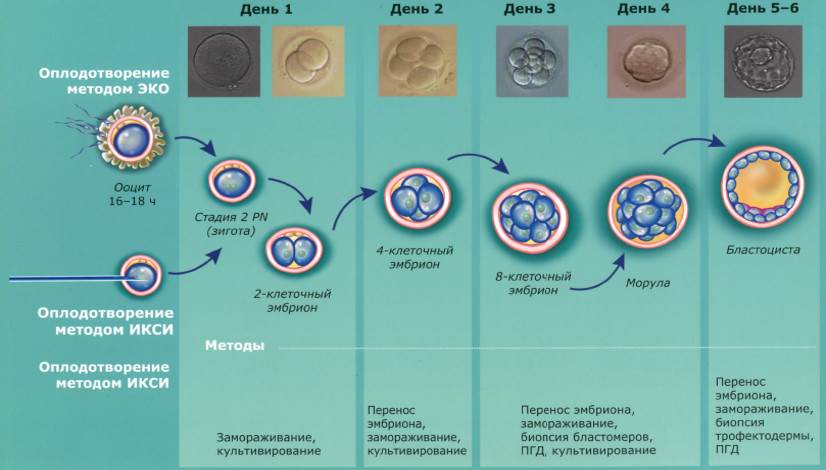

Эмбриогенез вторичноротых: основные стадии